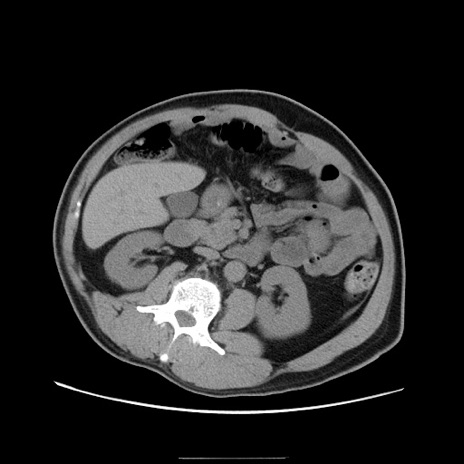

症例22(横断像)

【症例】50歳代男性

【主訴】腹痛

【現病歴】AVMからの被殻出血のため回復期リハ病棟入院中。 本日午後3時頃急に下腹部痛が出現した。

【既往歴】AVM、被殻出血、虫垂炎、高血圧

【身体所見】意識晴明、左半身不全麻痺、会話の理解は良好、36.5°C、腹部:膨隆、全体に板状硬、下腹部正中に圧痛点あり、反跳痛-、筋性防御不明、右下腹部にope scar

【データ】WBC 9400、CRP 0.06